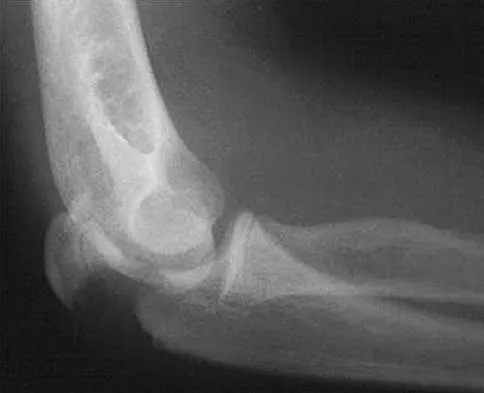

A 32-year-old woman sustained an injury to her left upper extremity in a motor vehicle accident. Examination reveals a 2-cm wound in the mid portion of the dorsal surface of the upper arm and deformities at the elbow and forearm; there are no other injuries. Her vital signs are stable, and she has a base deficit of minus 1 and a lactate level of less than 2. Radiographs are shown in Figures 9a and 9b. In addition to urgent debridement of the humeral shaft fracture, management should include

Explanation

With a severe injury to the upper extremity, the best opportunity for achieving a good functional result for a floating elbow is immediate debridement of the open fracture, followed by internal fixation of the fractures. The ability to do this depends on the patient's physiologic status. In this patient, the procedure is acceptable because she has normal vital signs and no chest or abdominal injuries, and normal physiologic parameters (base excess and lactate) show adequate peripheral perfusion. The surgical approaches will be determined by the associated injury patterns and open wounds. In this patient, the humerus was debrided and stabilized through a posterior approach as was the medial condyle fracture. The ulna was fixed through an extension of the posterior incision and the radius through a separate dorsal approach. Solomon HB, Zadnik M, Eglseder WA: A review of outcomes in 18 patients with floating elbow. J Orthop Trauma 2003;17:563-570.